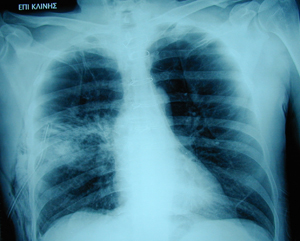

Εικόνα 2

Οπισθιοπροσθία ακτινογραφία θώρακος μετά από την τοποθέτηση του σωλήνα παροχέτευσης. Πλήρης έκπτυξη του πνεύμονος με εκτεταμένο υποδόριο εμφύσημα, λόγω ανεπαρκούς παροχέτευσης του αέρα μέσω του σωλήνα και πιθανώς λόγω μεγάλης διαφυγής αέρα. Επίσης πιθανόν να υπάρχει μονόπλευρο πνευμονικό οίδημα στο μέσο πνευμονικό πεδίο, λόγω απότομης έκπτυξης του πνεύμονα.